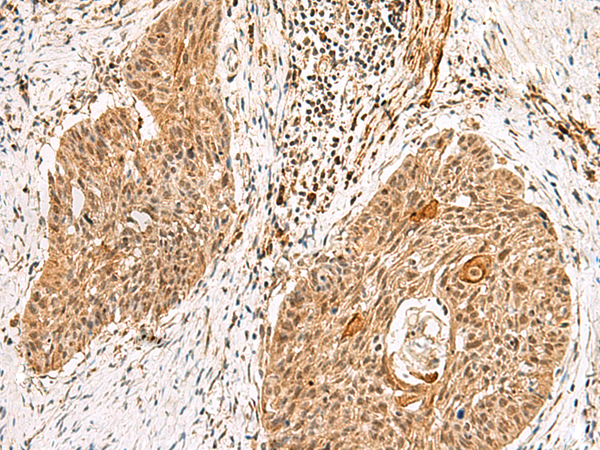

IHC positive control:

Human lung cancer and Human esophagus cancer

IHC Recommend dilution:

40-200